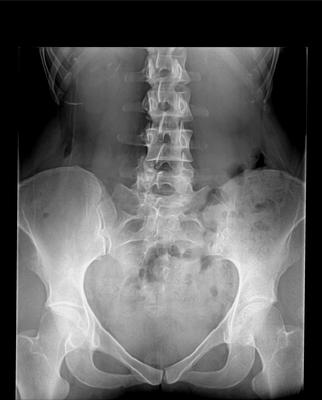

AP radiograph taken standing with 9mm heel insert on right side. Right side is on the right.

The 9mm lift looks about right. If you went any higher it might help your back more, but then distort the pelvis. All things being equal, I'd stay at 9mm.

(1)You clearly have a lumbarisation of the S1 segment; it's a fairly common anomaly and they certainly give more trouble in my experience. It's hereditary, and one of the reasons that back pain runs in families. Your children should also being lower back exercises every day before arising from bed. Prevention is better than a cure; 50% of them will have trouble as bad as yours, or worse.

That twist certainly contributes to your back pain; the facets at L5/L6 and L6/S1 are asymmetrical, and no, it's not correctable; in fact the lift may have made them look worse. It would be interesting to compare with a view of the pelvis without the lift, also taken standing.

(2)There are question marks about the right SI joint. It could be ankylosis, or even infection, but you'll notice the sacrum is much wider on the right, almost 30% more. I suspect the unusual appearance of the right SI may be due to the gross rotation of the sacrum. A CT scan might be in order.

(3)The femoral necks do appear shortened but I think (uncertain, out of my scope) probably also related to the lift, or the way your were standing. No CAM, very tiny, probably insignificant pincers, but certainly early degenerative change in the left hip; caused by a lifetime of short leg, can't change that. Your children should be assessed at some stage to prevent this happening in their hips; a lift at an early stage is problematic with kids but certainly worth a consideration.

The right acetabular space above is within normal limits, but you are right, the medial joint space does appear lessened and hazy; is the left hip stiff, painful?

The gross rotation of your sacrum is certainly unusual; then come all the chicken and egg questions; did the short leg, 9mm is quite a lot, cause it, or as your research questions suggests, did the pelvic distortion cause an apparent short leg?